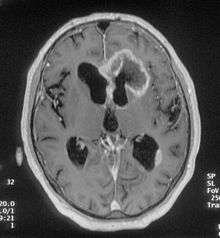

There are many different causes of frontal lobe epilepsy ranging from genetics to head trauma that result in lesions in the frontal lobes. Although frontal lobe epilepsy is often misdiagnosed, tests such as prolonged EEG monitoring and/or a MRI scan of the frontal lobes can be administered in order to reveal the presence of a tumor or vascular malformation. Unlike most epileptic EEGs, the abnormalities in FLE EEGs precede the physical onset of the seizure and aid in localization of the seizure's origin.[3] Medications such as anti-epileptic drugs can typically control the onset of seizures, however, if medications are ineffective the patient may undergo surgery to have focal areas of the frontal lobe removed.

The origins of frontal lobe seizures range from tumors to head trauma to genetics. Tumors account for about one third of all frontal lobe epilepsy cases. Low-grade tumors such as gangliogliomas, low-grade gliomas, and epidermoid tumors are most common, but many high-grade tumors were most likely once involved with seizures. Other lesions on the frontal lobe such as hamartomas and nodular heterotopias can cause frontal lobe symptoms as well. Birth defects such as vascular malformation are known to cause seizures, especially arteriovenous malformations and cavernous angiomas. Head trauma frequently causes damage to the frontal lobe and can cause seizures directly or indirectly through gliosis. Seizures originating directly from head trauma usually occur within a few months, but occasionally they can take years to manifest. On occasion encephalitis can cause frontal lobe seizures but it is most often associated with temporal lobe affliction. The main genetic cause of frontal lobe epilepsy is an autosomal dominant disease called Autosomal Dominant Nocturnal Frontal Lobe Epilepsy, which involves mutations in 2 nicotinic acetylcholine receptor genes. A genetic mutation on chromosome 22 has also been associated with another genetic form of the disorder.[1]